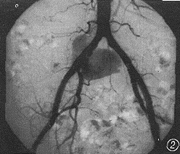

图2 DSA示右髂总动脉靠近髂内动脉处见一明显破口,对比剂由此溢出

DSA检查:腹主动脉管腔大小在正常范围,管壁光整,右侧髂总动脉有节段性管腔增宽,管壁欠规则,病变区见一明显破口,对比剂从破口溢出(图2),并在髂总动脉周围形成一巨大瘤腔(图3),可见其内对比剂完全充盈,边界清楚。病变段位于近髂内动脉开口处。